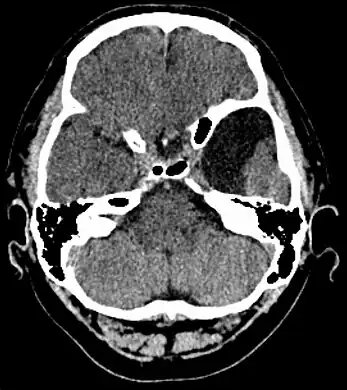

Axial CT showing a typical arachnoid cyst left temporal

Diagnosis is principally by MRI. Frequently, arachnoid cysts are incidental findings on MRI scans performed for other clinical reasons. In practice, diagnosis of symptomatic arachnoid cysts requires symptoms to be present, and many with the disorder never develop symptoms.